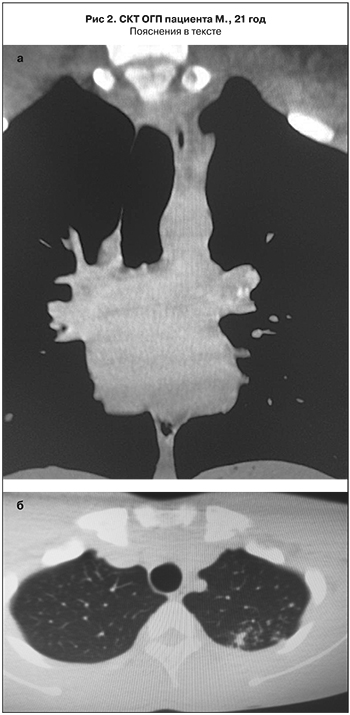

Клинический случай.

Студент М., 21 год, гражданин Республики Ангола. Проходил обучение на 1-м курсе Северо-Кавказского федерального университета. Поствакцинального знака нет. Симптомы интоксикации отсутствуют. Флюорография выполнена в ноябре 2016 г., патологии в легких не выявлено. В декабре 2016 г. проведена иммунодиагностика с АТР: гиперэргическая проба – 18 мм. В бронхопульмональной группе лимфатических узлов слева по данным СКТ ОГП – несколько кальцинатов размерами 4–5 мм (рис. 2, а). Также в С1–2 левого легкого определяются очаговые тени низкой интенсивности 0,5–0,6 см (рис. 2, б). Анализы мокроты на микобактерии туберкулеза всеми методами – отрицательные. Даны рекомендации по проведению основного курса лечения в связи с выявленной очаговой формой туберкулеза С1-2 левого легкого в фазе инфильтрации при отсутствии микобактерий туберкулеза.